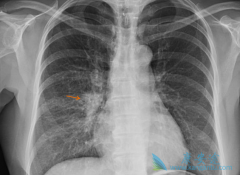

• 肺癌复发症状多发生在术后1-2年内

肺癌复发症状多发生在术后1-2年内

肺癌是当前世界上严重危害人类健康的恶性肿瘤,现已成为世界上因肿瘤致死的首要病因。在许多国家肺癌的发病率都呈上升趋势,尤其是在我国的城市当中其发病率和死亡率已上升为第一位。5年生存率低于15%,肺癌复发是导致死亡率高的主要原因。那 肺癌复发症 ...